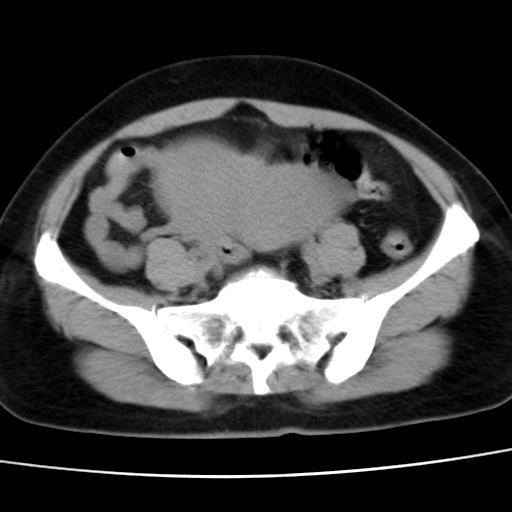

子宫多发肌瘤吗

多发性子宫肌瘤.

考虑多发子宫肌瘤,子宫直肠窝双囊性占位,另直肠周围脂肪密度增高,不知有何病史

支持考虑多发子宫肌瘤~!子宫直肠陷凹积液?

支持考虑多发子宫肌瘤~!子宫直肠陷凹积液!

子宫肌瘤,宫体部后方见液性密度影,是肠道还是子宫与直肠陷窝积液不好说,我觉得它的位置有点高

支持考虑多发子宫肌瘤!子宫直肠陷凹积液!

患者发热,而子宫直肠窝液性灶有明显边缘且局限且囊性,不除外为包裹性积液或脓肿

支持考虑多发子宫肌瘤,子宫直肠陷凹积液可能。

考虑多发子宫肌瘤

1)考虑子宫肌瘤可能性大。2)子宫后方囊性占位性病变,不排除卵巢囊肿可能。

考虑多发子宫肌瘤。子宫后方囊性占位性病变,不排除卵巢囊肿可能。